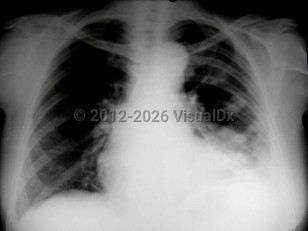

Chest pain, Pleural effusion, 50-59 year old Female

Pleural effusionPleural effusion

Hemothorax